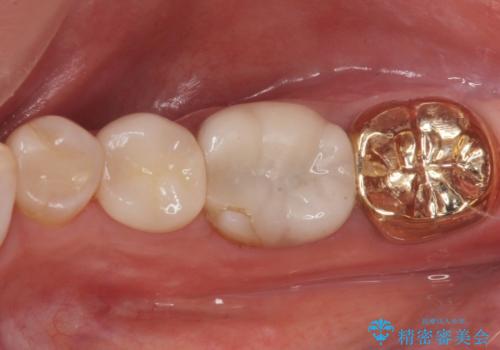

3. 昔いれたクラウンが割れたので金属の被せ物を入れたいの治療後